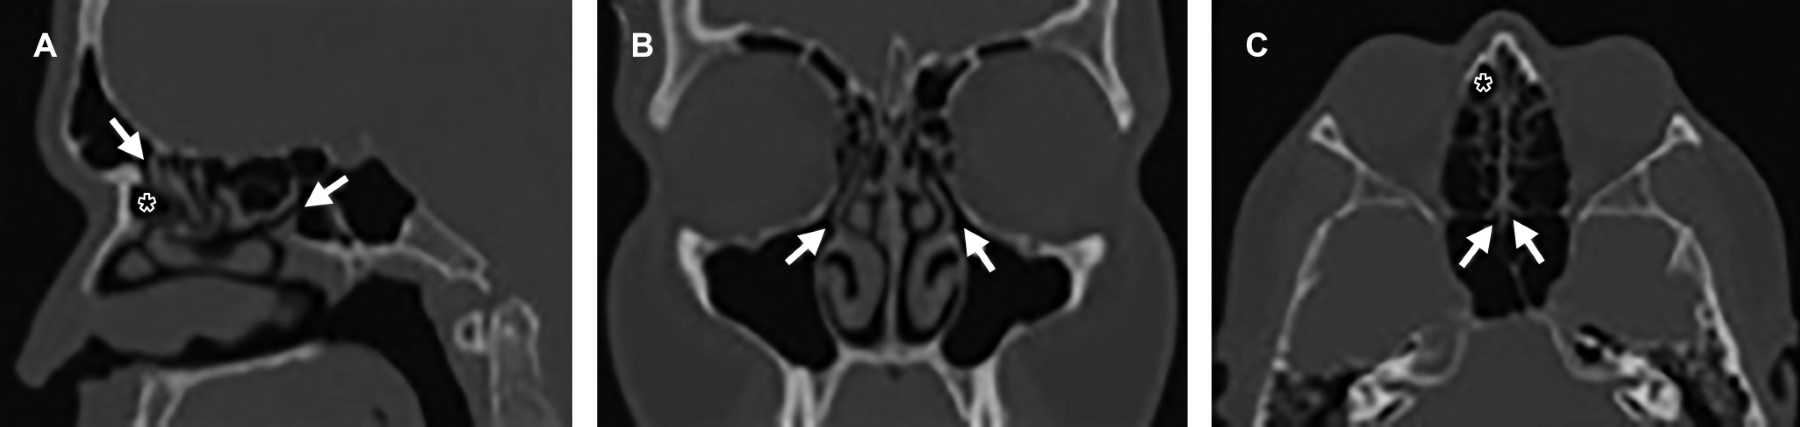

Para la profundidad de la fosa olfatoria, definida como relación vertical entre la lámina cribosa y techo etmoidal, se utilizó la clasificación de Keros (Figura 2). El más frecuentemente visualizado fue el tipo 2 con 59%, luego tipo 3 20% y por último el tipo 1 en 21%.

Para las variantes anatómicas que involucran el proceso uncinado, la atelectasia o contacto con la pared orbitaria no fue identificado en ninguno de los pacientes; sin embargo, la neumatización del mismo se observó en 7% (Figura 2).

En cuanto a la conformación de las celdillas etmoidales, la neumatización supraorbitaria (superior a la hendidura etmoidal) se encontraba presente en 46% de los pacientes estudiados, mientras que la neumatización adyacente al ostium del antro maxilar y a lo largo del piso de la órbita (celdillas infraorbitarias o de Haller) se observó en 10% (Figura 3). La celdilla de Onodi, definida como celdilla etmoidal posterior que se extiende al margen superior y lateral del seno esfenoidal, se visualizó en 12% de los estudios (Figura 3). La celdilla de agger nasi comprende la neumatización del dorso nasal, anterior a la inserción del cornete medio y corresponde a la variante estudiada más frecuentemente encontrada en hasta 95% (Figura 1).

Se identificó neumatización de cornete medio (a nivel del bulbo, lamela o ambas) en 60% al menos de forma unilateral. El giro paradójico de cornete medio, en el que la convexidad se proyecta hacia la línea media, se observó en 68% de los estudios al menos de forma unilateral (Figura 2).

La profundidad de fosa olfatoria (equivalente a la longitud de la lamela lateral), comprende tres tipos de acuerdo a la clasificación de Keros según la relación vertical entre la lámina cribosa y techo etmoidal medida en plano coronal.2 Se estima que la prevalencia en población general para el tipo 1 es de 30%, tipo 2 de 49% y tipo 3 de 21%, similar a lo encontrado en los estudios, siendo de 21, 59 y 20% respectivamente. Los tipos 1 y 3 presentan mayor riesgo de lesión iatrogénica, destacando meningitis, fístula de LCR y encefalocele, por comunicación de compartimento intracraneal a cavidades sinusales.2,3 Por lo que, en conjunto, los tipos 1 y 3 corresponden a 41% de los pacientes.

La orientación lateral del proceso uncinado en contacto con la pared orbitaria puede aumentar el riesgo de lesión de la pared medial de la órbita durante la uncinectomía, y el grado de neumatización puede disminuir la amplitud del infundíbulo. Una manipulación inadecuada supone fractura de lámina papirácea o cribosa que condicionaría trastornos olfatorios o fístulas de LCR.6 Si bien no se logró identificar atelectasia de proceso uncinado, la neumatización se identificó en 7% de los pacientes estudiados, mientras que en la población general se observa en aproximadamente 4%.2,7

La celdilla etmoidal más anterior, que se extiende anteriormente en el hueso lacrimal, también recibe el nombre de "celdilla de agger nasi". Superior a la misma, se puede identificar diverso número y grado de neumatización de celdillas frontoetmoidales. Su relevancia radica en que provee un acceso quirúrgico al ostium primario del seno frontal y su resección permite permeabilizar el drenaje, en los casos en los que exista patología del mismo. Wormald y colaboradores mencionan y validan la clasificación de "International Frontal Sinus Anatomy Classification (IFAC)" para describir las variantes anatómicas de la región frontal previo a cirugía endoscópica funcional,11 para con ello disminuir la necesidad de reintervención o persistencia de sintomatología. Se identifican en aproximadamente 3 a 100% de los pacientes, margen amplio a causa de su definición operacional.6,12 En nuestra población se utilizó el concepto anteriormente mencionado, identificándolas en 95% de los estudios. Por ello es imperativo no sólo reconocerlas, sino profundizar en la descripción del grado de neumatización y relación respecto al ostium de drenaje del seno frontal en el reporte tomográfico.

Los cornetes medios presentan una gran variedad de variantes anatómicas. En población general, se identifica su neumatización en aproximadamente 15-35% según el segmento involucrado (lamelar, bulbar o ambas). El giro paradójico se observa en 3 a 30% de los pacientes. Para este estudio se consideró como presente la neumatización de cualquier segmento del cornete al menos de forma unilateral. El giro paradójico se definió como convexidad de orientación medial, considerándose presente al menos de forma unilateral. Fueron visualizadas en 40 y 32% de los pacientes respectivamente.